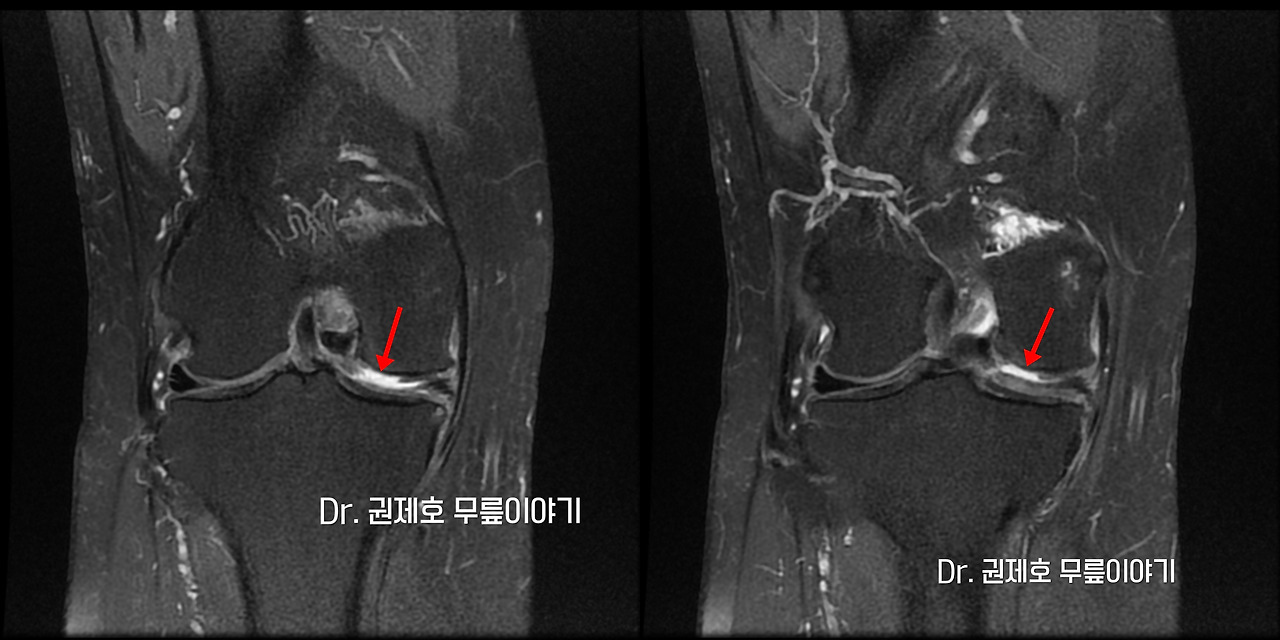

무릎연골줄기세포치료 (16)-horz.jpg

무릎의 연골 결손을 확인하기 위한 검사는 MRI입니다. 사진에서 보면 연골이 깨진 모습이 관찰되고 있는 것을 확인하실 수 있습니다.